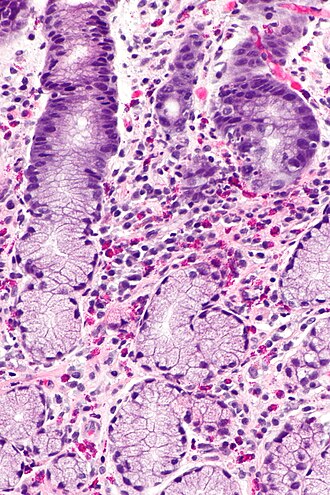

Stomach with eosinophilia. H&E stain. | |

| LM | abundant eosinophils (>=127 eosinophils/mm2) |

Eosinophilic gastritis, abbreviated EG, is an uncommon inflammatory process of stomach characterized by abundant eosinophils.

- Abundant eosinophils -- >=127 eosinophils/mm2.[3]

- 30 eosinophils/HPF, if the field diameter of 1 HPF is 0.55 mm.

- Normal range:[3]

- <38 eosinophils/mm2.

- Typically ~16 eosinophils/mm2.

- Mild eosinophilia is seen in:[3]

- Crohn's disease ~ 31 eosinophils/mm2 (range: 0-203 eosinophils/mm2).

- Helicobacter gastritis ~ 25 eosinophils/mm2 (range: 0-219 eosinophils/mm2).